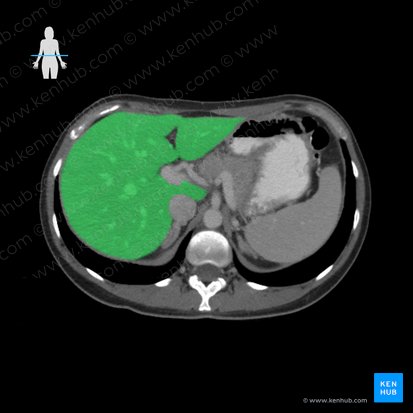

Anatomy of the liver

Anatomically, the liver is viewed as having four main lobes. There is a smaller left lobe and a larger right lobe (that are separated along the attachment of the falciform ligament), as well as a caudate and a quadrate lobe (which are part of the anatomical right lobe).

However, the distribution of the portal blood supply and biliary drainage of the liver allows the organ to be functionally divided into four sectors, which are subsequently divided to give a total of eight segments.

The division of the liver into equally sized functional left and right lobes is done by drawing a line through the midline of the gallbladder and the inferior vena cava. As opposed to the anatomical division that results in the caudate and quadrate lobes being between the right and left anatomical lobes of the liver, this division results in the caudate and quadrate lobes being a part of the functional left lobe.